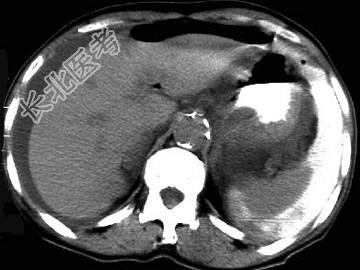

- 单项选择题男,44岁, 突然中上腹痛,压痛, 反跳痛,腹肌紧张, 发热,白细胞计数升高, CT检查如图,最可能的诊断是 ( )

A、急性胰腺炎

B、慢性胰腺炎

C、胃小弯溃疡穿孔

D、胰腺癌

E、胃癌